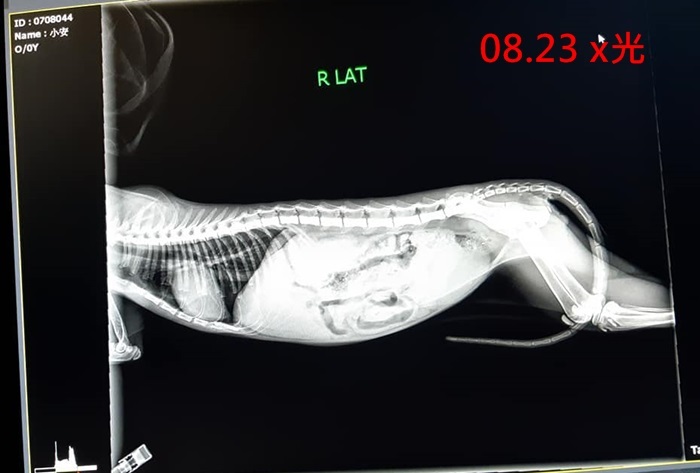

醫師先為小安施行麻醉將直腸復位,並進行血檢、x光,小安除了直腸脫出問題之外,左眼有萎縮變小情況及淚眼嚴重,其他狀況都還良好,小安在直腸進行復位後即住院觀察,小安年紀尚幼,單純活潑,在住院治療幾日,身體情況變好些就開始想要玩耍,模樣討喜可愛,只是他一痾便便直腸就會掉出,且拉出許多蛔虫,於是醫師餵他吃驅虫藥,希望驅虫完成後或許可以改善直腸脫出情況,只是小安吃了幾次驅虫藥並進行糞檢,確定無虫後但仍是便便就會脫肛,醫師評估可能須要進行腸固定術或截腸手術,於是醫師在10月17日為小安進行了結腸固定術並完成結紮,術後截至出院,小安便便時都已無再發生脫肛情況了。

2018-08-23進行直腸脫出復位、血檢、住院。

住院費、x光、糞檢、驅虫Baycix、抗生素針,眼藥。